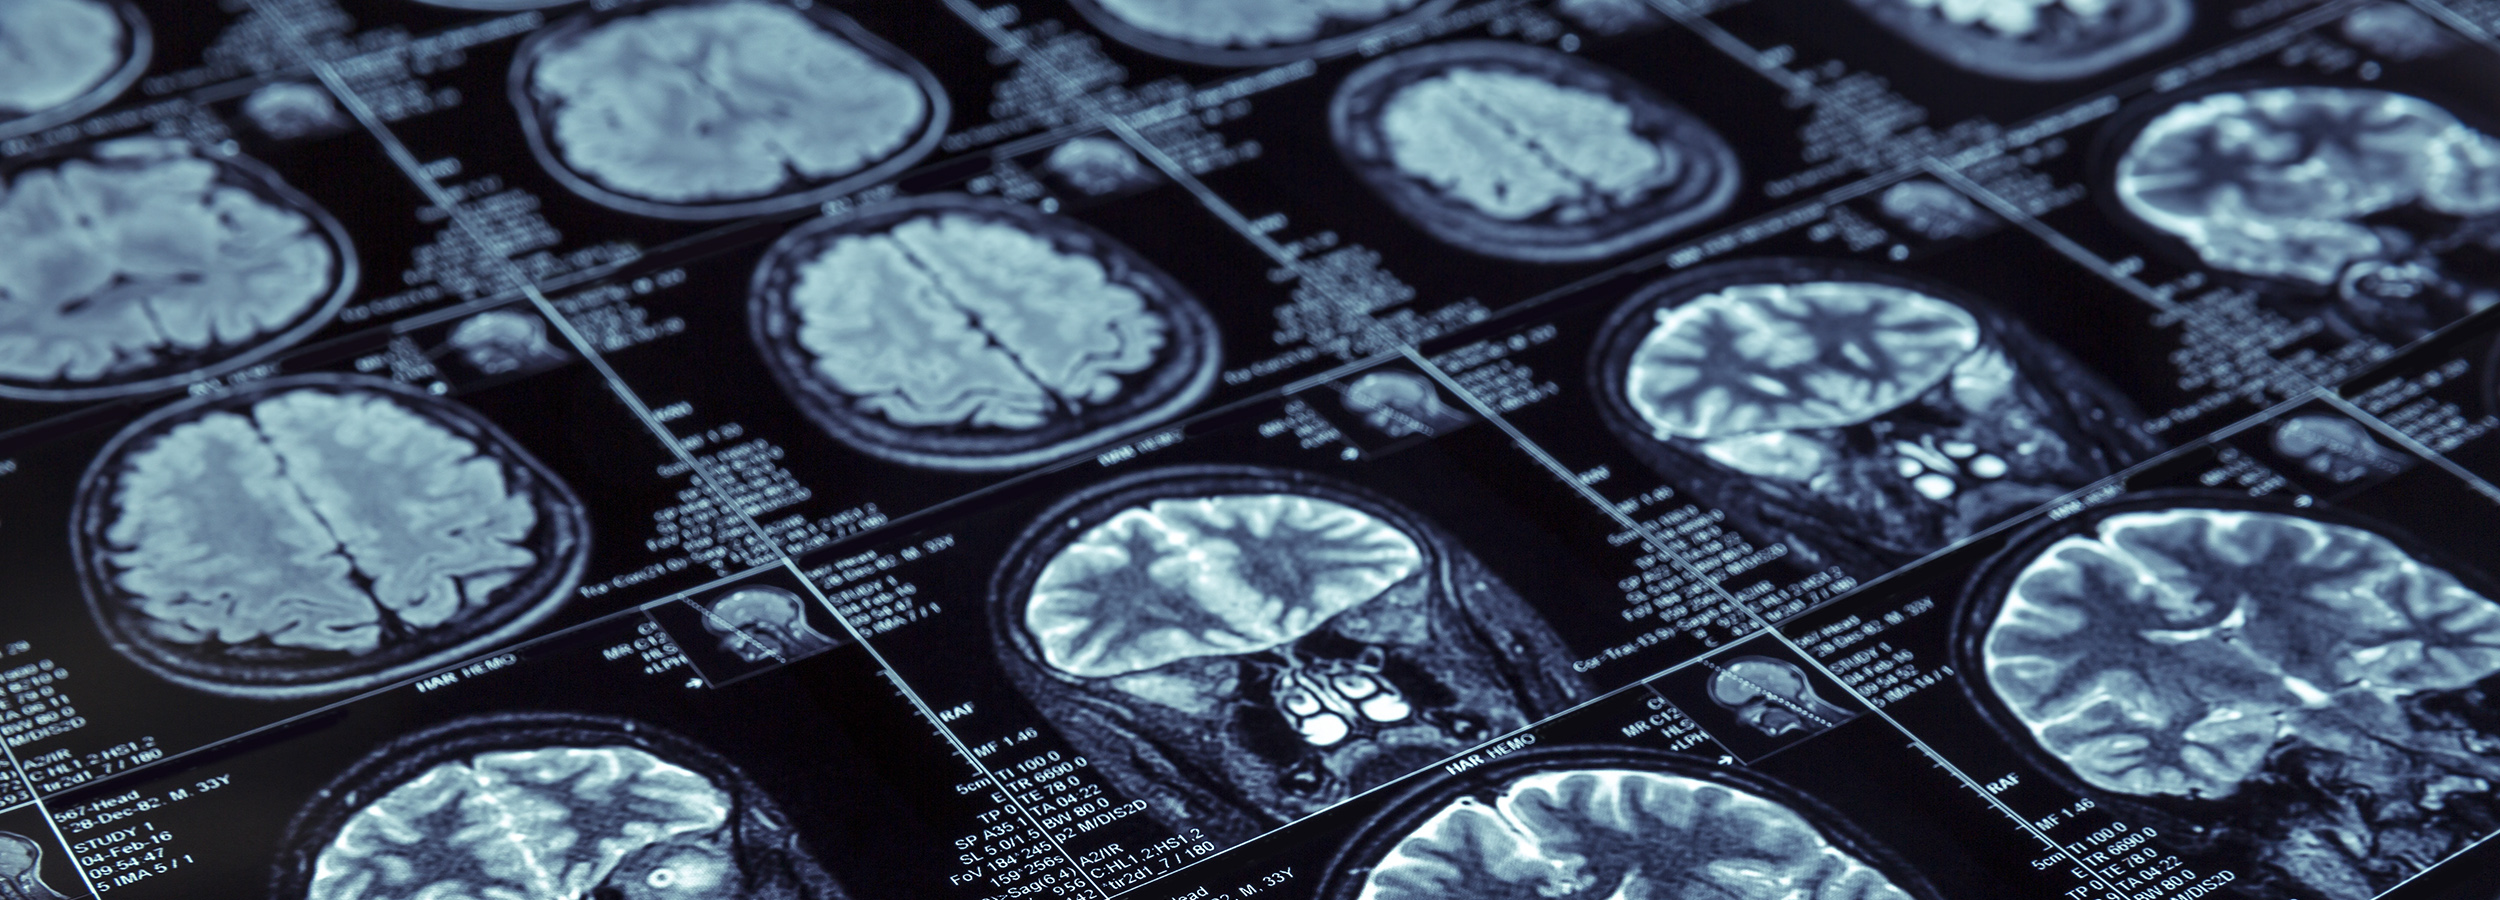

최첨단 3.0T MRI를 이용한 세밀하고 선명한 촬영 결과로 빠른 진단과 치료가 가능합니다.

더자인병원은 차세대 MRI인 3.0T MRI를 도입해 가장 미세한 혈관이 모여 있는 신체 부위인 뇌를 정밀하게 관찰할 수 있어 진단이 어려웠던 소혈관질환, 뇌신경질환 등의 진단율을 높이는 동시에 전문 의료진이 치료합니다.